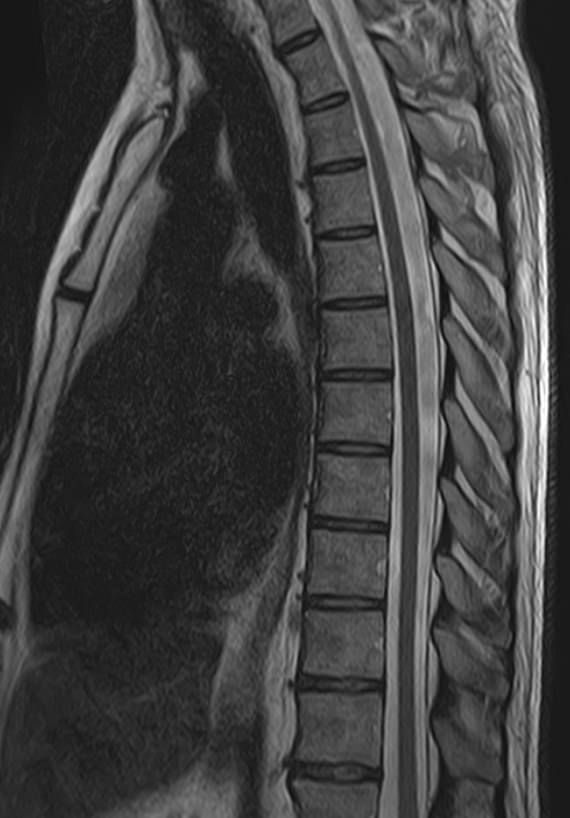

В нашей клинике мы проводим комплексное исследование, включающее МРТ головного мозга и всех отделов позвоночника. Методика комплексного обследования применяется при наличии у пациента сочетанных поражений головного мозга, спинного мозга и позвоночного столба.

Стандартная МРТ головного мозга дает важную информацию о состоянии и структуре мозговой ткани для выявления большого числа заболеваний, в том числе опухолевых образований, демиелинизирующих заболеваний, воспалительных процессов головного мозга и мозговых оболочек.

При подозрении на распространенный процесс с поражением различных уровней позвоночника целесообразно проведение МРТ для диагностики дегенеративно-дистрофических заболеваний, травматических, воспалительных изменений, а также опухолевых процессов позвоночника. Метод позволяет оценить состояние структур позвонков, позвоночного канала с расположенным в нем спинным мозгом и окружающих мягких тканей, кроме того, является основным способом диагностики демиелинизирующих заболеваний спинного мозга.

Исследование проводится на современном томографе TOSHIBA VANTAGE TITAN 1,5 Тесла. За счет высокой индукции магнитного поля аппарат обладает  высокой разрешающей способностью, что позволяет проводить точную диагностику заболеваний центральной нервной системы и позвоночника.